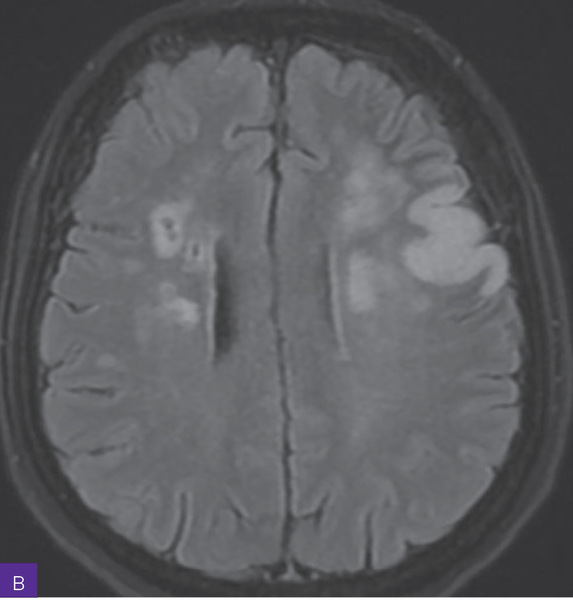

Rycina 2A, B. Rezonans magnetyczny głowy. Widoczne rozsiane ogniska i nieco większe obszary niedokrwienne w fazie ostrej z zakresu unaczynienia gałęzi tętnicy lewej środkowej mózgu, a także rozsiane zmiany wcześniej przebytych ognisk niedokrwiennych z zakresu unaczynienia tętnicy prawej środkowej mózgu

Diagnostykę poszerzono o badanie rezonansu magnetycznego (MR) w protokole udarowym. W badaniu opisano rozsiane ogniska i nieco większe obszary niedokrwienne w fazie ostrej z zakresu unaczynienia gałęzi tętnicy lewej środkowej mózgu, a także rozsiane zmiany wcześniej przebytych ognisk niedokrwiennych z zakresu unaczynienia prawej tętnicy środkowej mózgu (ryc. 2).